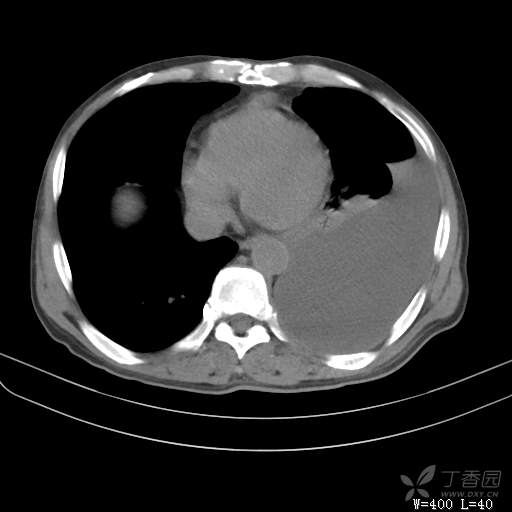

简要病史:胸闷、憋气伴低热1月

体格检查:T:37.6℃;P:92次/分;R:20次/分;Bp:100/60mmHg,神清,呼吸平稳,周身未触及肿大淋巴结,右肺及左上肺叩诊清音,左下肺叩诊浊音,右肺及左上肺呼吸音粗,左下肺未闻及呼吸音,心率92次/分,律齐,无杂音。腹部平坦,软,全腹无压痛,无反跳痛及肌紧张,肝脾肋下未触及,双下肢无水肿。

临床诊断:左侧胸腔积液